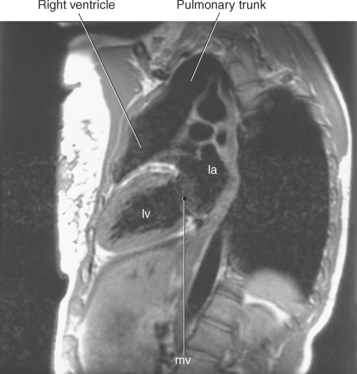

Blood travels to and from the heart through the great vessels, which include the aorta, pulmonary arteries and veins, and superior and inferior venae cavae (Figures 6.54 and 6.55). The aorta is the largest artery of the body and can be divided into the ascending aorta, aortic arch, and descending aorta. The ascending aorta begins at the base of the left ventricle at the level of the sternal angle, then curves superiorly and posteriorly as the aortic arch over the root of the left lung. The top of the aortic arch is approximately at T3 (Figures 6.56 and 6.57). The arch continues as the descending aorta posterior to the left bronchus and pulmonary trunk, on the left side of the vertebral body of T4 (Figures 6.58 and 6.59). The descending aorta passes slightly anterior and to the left of the vertebral column as it descends through the thoracic and abdominal cavities (Figure 6.60). While in the thoracic cavity, the descending aorta is commonly called the thoracic aorta, and while in the abdominal cavity, it is called the abdominal aorta. The pulmonary trunk is the origin of the right and left pulmonary arteries and lies entirely within the pericardial sac. It arises from the right ventricle and ascends in front of the ascending aorta, courses posteriorly and to the left, where it bifurcates at the level of the sternal angle (T4) into the right and left pulmonary arteries (Figures 6.61 through 6.63). The pulmonary trunk is attached to the aortic arch by a fibrous cord called the ligamentum arteriosum, the remnant of an important fetal blood vessel (ductus arteriosus) that links the pulmonary and systemic circuits during fetal development (Figures 6.54 and 6.61). The right pulmonary artery courses laterally, posterior to the ascending aorta and superior vena cava, and anterior to the esophagus and right mainstem bronchus, to the hilum of the right lung. At the root of the right lung, the right pulmonary artery divides into two branches, with the lower branch supplying the middle and inferior lobes and the upper branch supplying the superior lobe (Figures 6.61 through 6.64). The left pulmonary artery, shorter and smaller than the right, is also the most superior of the pulmonary vessels. It travels horizontally, arching over the left mainstem bronchus, and enters the hilum of the left lung just superior to the left mainstem bronchus (Figures 6.61 through 6.64). Within the lungs, each pulmonary artery descends posterolateral to the main bronchus and divides into lobar and segmental arteries, continuing to branch out and to follow along with the smallest divisions of the bronchial tree (Figures 6.61 and 6.64). Located inferior to the pulmonary arteries are the four pulmonary veins, two each (superior and inferior) extending from each lung to enter the left atrium (Figures 6.54, 6.55, 6.61, and 6.64 through 6.68). They commence in a capillary network along the walls of the alveoli, where they are continuous with the capillaries of the pulmonary arteries. The venous capillaries merge to form small vessels that unite successively to eventually form a single trunk for each lobe: three for the right and two for the left lung. Frequently the trunk from the middle lobe of the right lung unites with the trunk from the upper lobe, forming just two trunks on the right side prior to entering the left atrium. The right superior pulmonary vein collects blood from the upper lobe segments of the right lung and passes anterior and inferior to the right pulmonary artery, behind the superior vena cava. The right inferior pulmonary vein receives blood from the right lower lobes of the lung and crosses behind the right atrium to the left atrium (Figures 6.61 and 6.69 through 6.71). The left superior pulmonary vein receives blood from the left upper lobe of the left lung and courses anterior and inferior to the left main bronchus as it enters the left atrium. The left inferior pulmonary vein drains the inferior lobe of the left lung and passes toward the left atrium anterior to the bronchi (Figures 6.61 and 6.72 through 6.74). The pulmonary veins course more horizontally than the pulmonary arteries and are ultimately oriented toward the left atrium. At the root of the lungs, the pulmonary veins are anterior to the pulmonary arteries, which are anterior to the bronchus. While within the lungs, the branches of the pulmonary arteries are anterior to the bronchi, which are anterior to the pulmonary veins. The superior and inferior venae cavae are the largest veins of the body. The superior vena cava is formed by the junction of the brachiocephalic veins, posterior to the right first costal cartilage, and carries blood from the thorax, upper limbs, head, and neck (Figure 6.24). As it travels inferiorly, it is located posterior and lateral to the ascending aorta before entering the upper portion of the right atrium (Figures 6.54 through 6.59). The inferior vena cava is formed by the junction of the common iliac veins in the pelvis and ascends the abdomen to the right of the abdominal aorta and anterior to the vertebral column. It passes through the caval hiatus of the diaphragm and almost immediately enters the inferior portion of the right atrium (Figures 6.75 and 6.76).

Figure 6.60 Sagittal, T1-weighted MR scan with aortic arch and descending aorta.

Key: ar, aortic arch; da, descending aorta; mbr, mainstem bronchi; rPA, right pulmonary artery; ab, aortic bulb; la, left atrium; rv, right ventricle.

In an effort to standardize nomenclature for tomographic imaging of the heart, the Cardiac Imaging Committee of the Council on Clinical Cardiology of the American Heart Association published a statement recommending that all cardiac imaging modalities use the same nomenclature for defining tomographic imaging planes. Their recommendation stated that “all cardiac imaging modalities should define, orient, and display the heart using the long axis of the left ventricle and selected planes oriented at 90-degree angles relative to the long axis.” Their second recommendation stated, “The names for the 90-degree oriented cardiac planes used in all imaging modalities should be short axis, vertical long axis, and horizontal long axis. These correspond to the short-axis, apical two-chamber, and apical four-chamber planes traditionally used in 2D echocardiography” (Figure 6.77). We will follow these recommendations for labeling cardiac images throughout this text. In magnetic resonance (MR) imaging, each successive acquisition provides the landmarks for planning the next acquisition (view) and provides a logical method to obtain 90-degree viewing of the heart according to its intrinsic short and long axes. Several different methods can be used to obtain views of the cardiac planes during an examination, of which we provide an example of one method. To obtain the vertical long axis (VLA) view, an oblique coronal image can be positioned parallel to the interventricular septum, directly through the left atrium and ventricle (Figures 6.78 and 6.79). This plane closely approximates the right anterior oblique projection used in cineangiography and the two-chamber view used in echocardiography. The horizontal long axis (HLA) view can be obtained by angling an oblique coronal image to bisect the left ventricle, mitral valve, and left atrium (Figures 6.80 and 6.81). The HLA view demonstrates the four cardiac chambers and is comparable with the four-chamber plane used in echocardiography. The short axis (SA) view can be obtained by using the HLA image to prescribe an oblique plane through the right and left ventricles, oriented perpendicular to the interventricular septum (Figures 6.82 and 6.83).